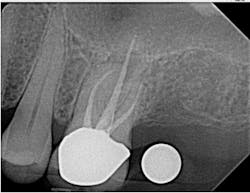

I also use my ProMax 3D Classic for endodontic evaluation and treatment when needed (figures 6–8). A small field of view (5 cm x 5 cm) image can be taken to limit radiation exposure and focus on the tooth in question. It has come in handy when looking for the second mesiobuccal (MB2) canal in maxillary molars and makes identifying periradicular lesions much easier than periapical radiographs.